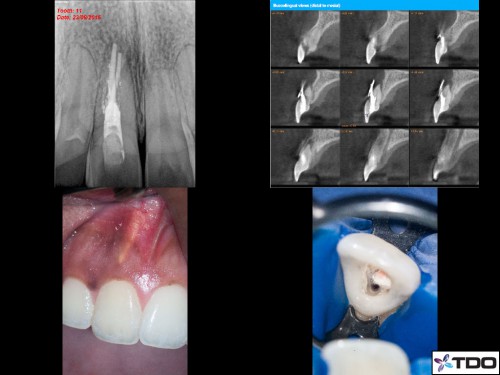

#7 referred with a separated file/internal resorption/calcification/apical split

#7 referred with a separated file/internal resorption/calcification/apical split > History of trauma and a I/O […]